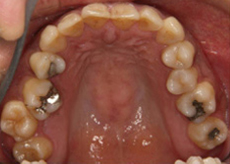

初診時の口腔内写真では左の咬合平面が下がっていました。

左上下顎臼歯部に著しい叢生があり、下顎臼歯部が大きく舌側へ傾斜していました。左はもちろん、右側も歯並びが崩れていて、右ではほとんど咬んでいなかったそうです。